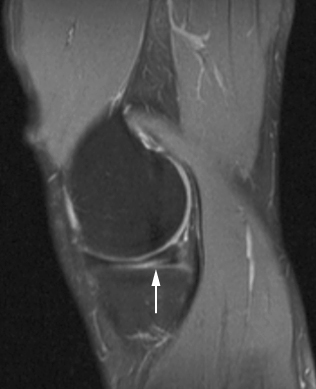

膝盖半月板的损伤,根据病人的磁共振检查结果可以分为4级,即0级、I级、II级、III级,目前大部分的病人都是根据磁共振检查上的纸质报告,来判断自己半月板损伤的程度,具体分级如下:

0级:正常的半月板,磁共振检查结果未见异常;I级:不与半月板关节面相连的病灶;II级:线性病灶,可延伸至关节囊缘,但仍为设计半月板的关节面缘;III级:半月板内的信号波及一个关节面或者两个面的。